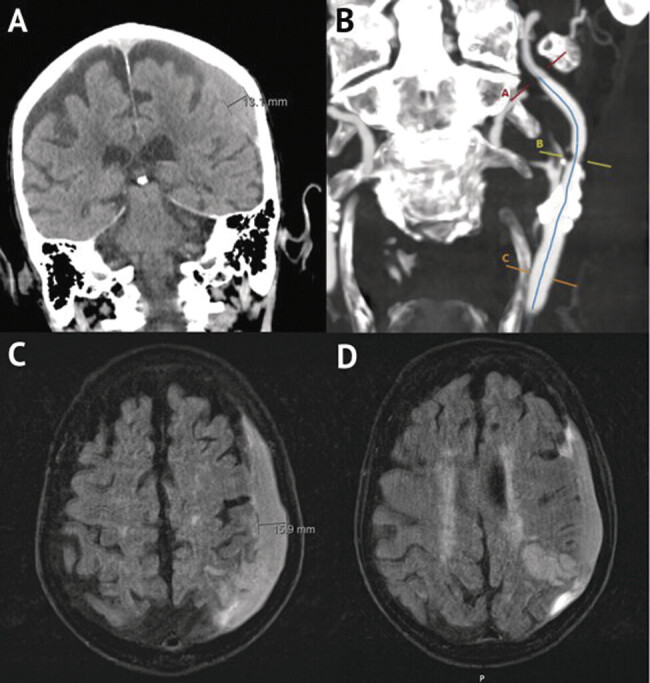

Case presentation: A 90-year-old male presented after 6 days of slurred speech and severe headache. A head computed tomography (CT) revealed a left-sided 13-mm subdural hemorrhage, and neck CT angiography revealed left internal carotid artery stenosis at 50%. The carotid stenosis was treated with a standard carotid endarterectomy at the carotid bulb. Despite direct catheterization of the external carotid artery, selective catheterization of the MMA was not feasible. Instead, coils were placed in the left internal maxillary artery spanning the left MMA origin, and the right MMA was selectively embolized using a standard transradial approach. Postoperative CT showed a reduction in subdural hematoma (SDH) size, and the patient was discharged in stable condition on postoperative day 6.